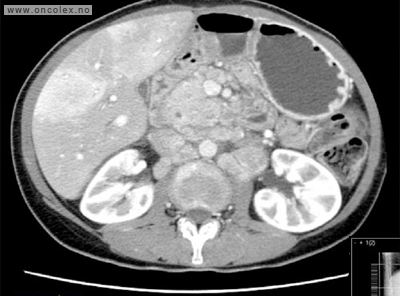

CT  med kontrast er den mest brukte røntgenundersøkelsen. Kontrastvæsken gis gjennom en kanyle (venflon) i armen. Svulster i leveren synes oftest best på MR. MR eller CT-tynntarm kan påvise nevroendokrine svulster i tynntarmen som ikke ses på vanlig MR/CT.

Bildeeksempler